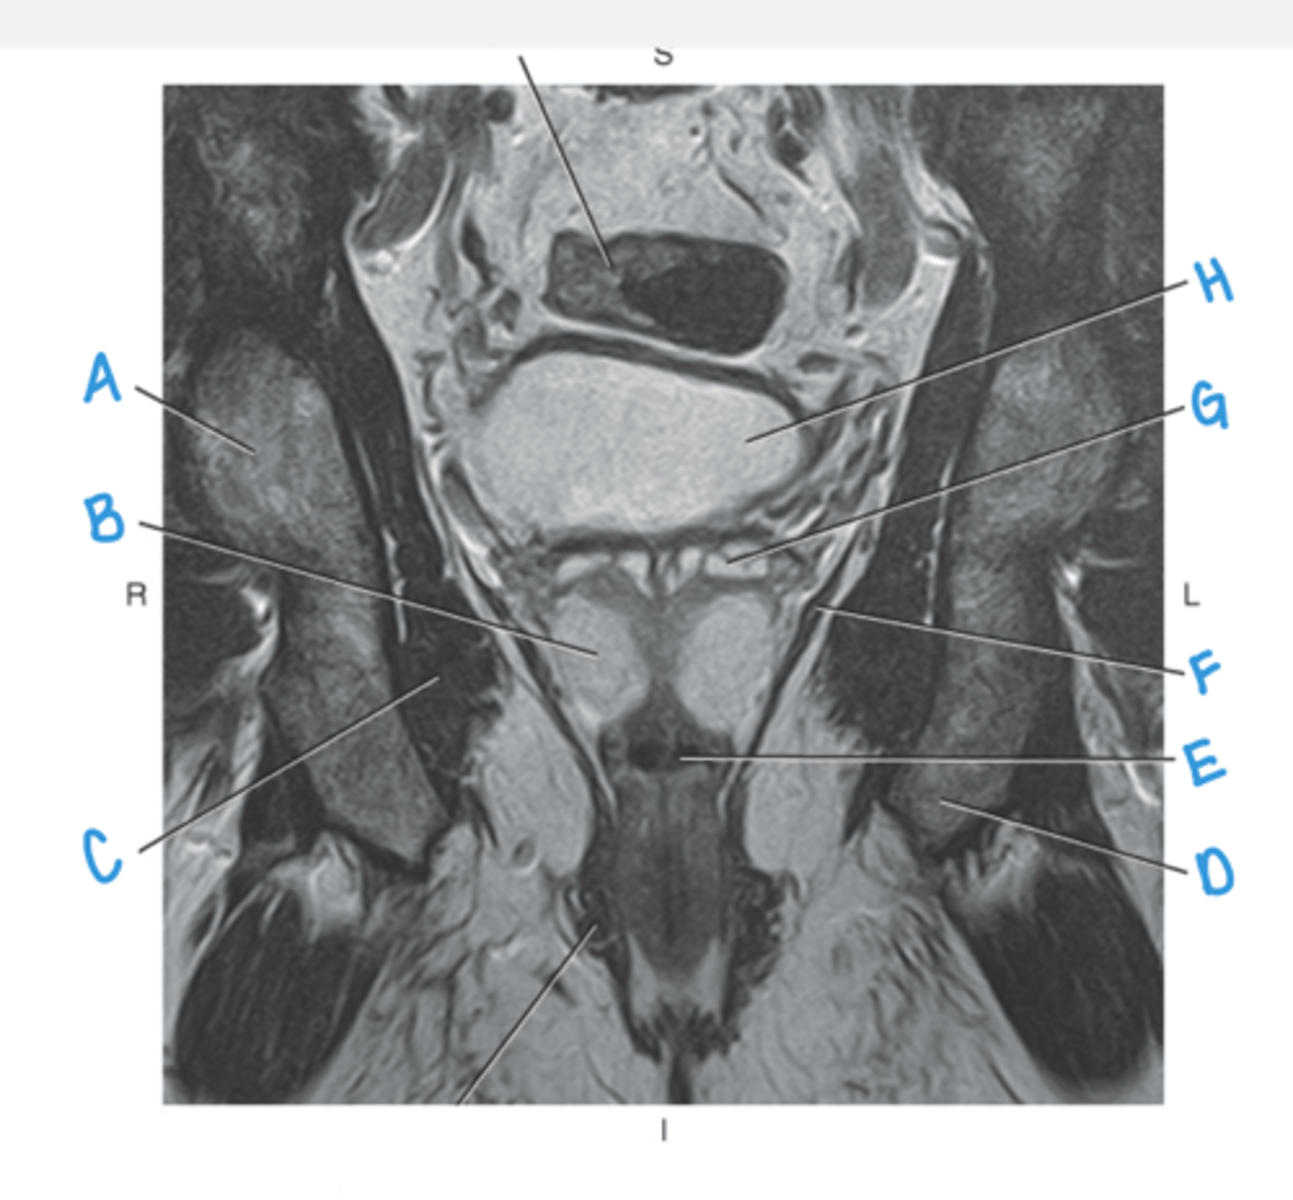

sacral promontory

A

sigmoid colon

B

vagina

C

rectum

D

urethra

E

pubic symphysis

F

retro-pubic space

G

bladder

H

uterus

I